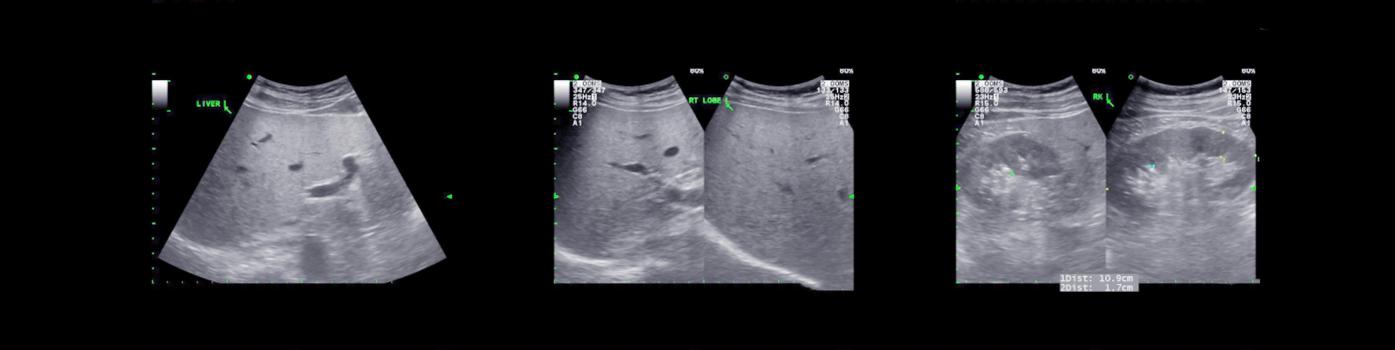

Réalisée au lit du malade, cette méthode diagnostique non invasive et non irradiante est utilisée comme un complément à l’évaluation des patients et des patientes. Elle intègre une multitude de données cliniques et des explorations échographiques ciblées : cardiaques (ex. : épanchement péricardique), pulmonaires (ex. : épanchement pleural, pneumothorax), urinaires (ex. : dilatation des voies urinaires), abdominales (ex. : hémorragie péritonéale, anévrisme de l’aorte), etc. L’ultrasonographie ciblée permet également de contrôler des procédures semi-invasives (ex : ponctions liquidiennes et vasculaires écho-guidées). « Sorte de stéthoscope amélioré, le POCUS aide à répondre spécifiquement à des questions binaires qui découlent de notre raisonnement clinique. Il nous apporte une expertise technique rigoureuse, néanmoins limitée par rapport à l’approche radiologique, plus descriptive et avancée », explique le Dr Olivier Grosgurin, médecin adjoint agrégé au Service de médecine interne générale et au Service des urgences.